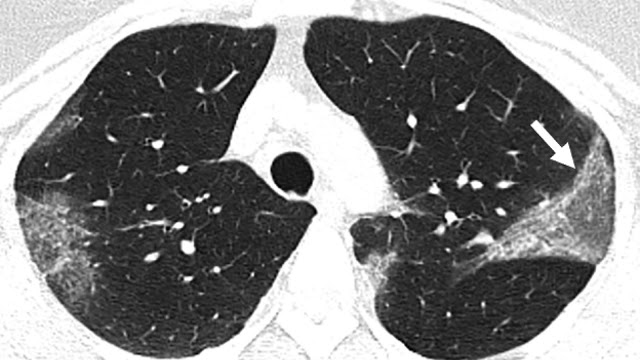

저는 의사로서 코비드 19에 걸렸다가 회복된 사람의 폐가 30년간 담배를 핀 흡연가의 폐보다 더 형편없이 망가져 있는 것을 보고 이 병이 단순한 폐렴이 아니라는 것을 알고 경악을 금치 못했습니다.

게다가 작년 7월에 란셋에 보고된 논문에 의하면 코비디 19에서 완전히 회복한 후에 3개월이 지난 시점에서 60% 의 환자에거서 폐손상이 CT scan을 통해서 확인할 수 있었다는 보고도 있습니다.

열도 없고 단지 마른 기침, 몸살 증세, 피곤한 것이 전부였으나 저는 그 분의 폐 엑스레이를 보고 바로 입원시켰습니다.

엑스레이를 보니 양쪽 폐를 모두 광범위하게 침범하는 폐렴인데 코비드 19란 것을 바로 알려 차렸습니다.

무증상 감염자의 상당수가 이런 폐를 갖고 있다고 하는 충격적인 보고도 있으니 제가 장담하건데 향후 3년 안에 만성 폐질활 환자 수가 미국에서 폭발적으로 늘어나는 시대가 올 겁니다.

당연히 모든 감염자는 아닙니다. 중환자실까지 가지 않고, 회복한 사람의 60% 이상이라고 란셋에 나와 있습니다. 무증상자의 몇 %가 저런지는 좀 더 깊은 조사가 필요하지만, 일부 의사들의 주장을 보면, 생각보다 많다고 합니다. 이 환자는 폐사진에 비해서, 증세가 너무 경미해서, 의료진을 놀라게 한 케이스구요. 그러 것이 여러번 있었습니다.